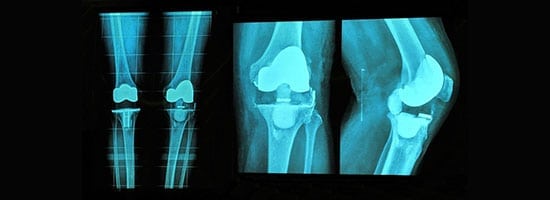

Conventional joint replacement surgery is a well-established procedure used to treat joint pain, stiffness, and dysfunction caused by arthritis or other degenerative joint conditions. During this surgery, the damaged or worn-out parts of the joint are removed and replaced with an artificial prosthesis, which is designed to mimic the natural movement of the joint. The most common joints replaced are the hip and knee, although shoulder, elbow, and ankle replacements are also performed. This procedure has been successfully performed for decades and remains a highly effective treatment option for patients who have not responded to conservative treatments such as medication and physical therapy.

In conventional joint replacement surgery, the surgeon makes a large incision over the affected joint to access the underlying bone and cartilage. The damaged parts of the joint are carefully removed, and the artificial prosthesis is then fitted into place. The prosthesis is typically made of materials such as metal, plastic, or ceramic, depending on the joint and the patient's specific needs. The goal is to restore function, reduce pain, and improve the patient's quality of life. Although the procedure is highly successful in the majority of cases, recovery times can be longer compared to newer, less invasive techniques like robotic-assisted surgery.